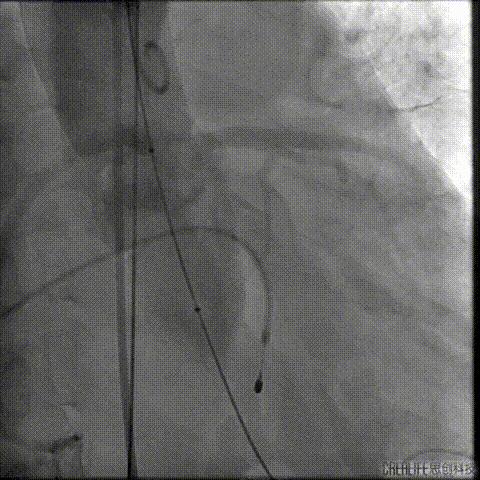

TAVR术后3日Hb较前下降 (63g/L)

CT提示左侧腹膜后、髂窝及腹股沟区巨大血肿

行急诊手术 腹主动脉及左侧股动脉造影

左侧股动脉见造影剂外渗

球囊压迫后植入覆膜支架

复查造影